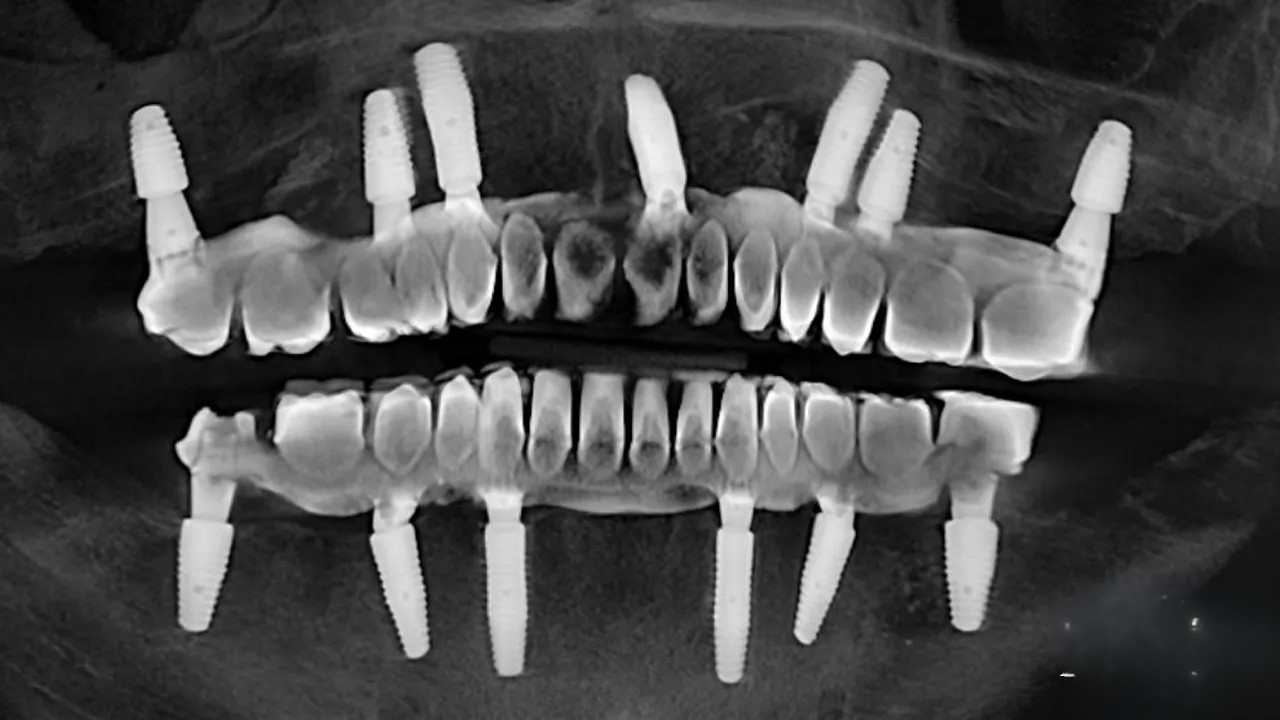

ایمپلنت دندان (Dental Implant) روشی علمی برای جایگزینی دندانهای ازدسترفته است که از یک فیکسچر تیتانیومی (Implant Fixture) بهعنوان ریشه مصنوعی استفاده میکند. این فیکسچر در استخوان فک کاشته شده و پس از جوش خوردن با استخوان (Osseointegration)، روکش دندانی (Crown) روی آن نصب میشود. روشهای مختلف ایمپلنت—سنتی، فوری، پانچ و دیجیتال—هر یک ویژگیها و کاربردهای خاص خود را دارند. در ادامه، هر روش را با جزئیات بررسی میکنیم.